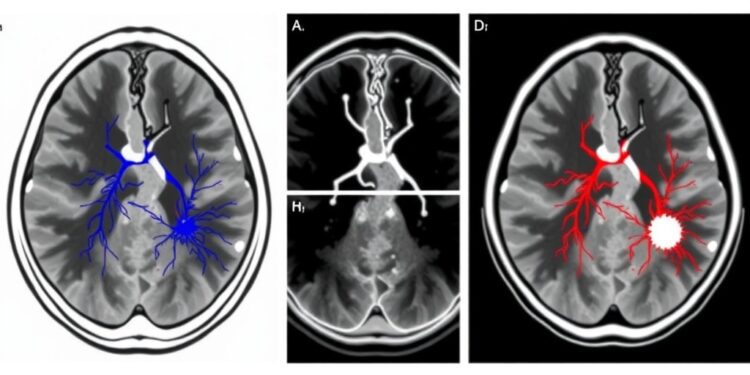

One significant aspect of the study is the established correlation between DCE-MRI parameters and vascular architecture within tumors. Such correlations underscore the biological underpinnings of tumor development and the critical role that microvascular density plays in tumor growth and metastasis. Understanding these dynamics could lead to refined diagnostic protocols that facilitate enhanced prognosis for patients presenting with SSPNs. This is especially relevant given the complexity of the vascular microenvironment in neoplastic diseases, where variations can often go unnoticed without advanced imaging techniques.

Moreover, the study emphasizes the potential of DCE-MRI in differentiating malignancies based on the characteristics of the vascular microenvironment. Utilizing these advanced imaging biomarkers, healthcare providers can adopt a more nuanced approach to diagnosing SSPNs. Rather than solely relying on standard morphological features, the incorporation of hemodynamic parameters offers a robust framework for understanding tumor biology, which may significantly impact treatment decisions.